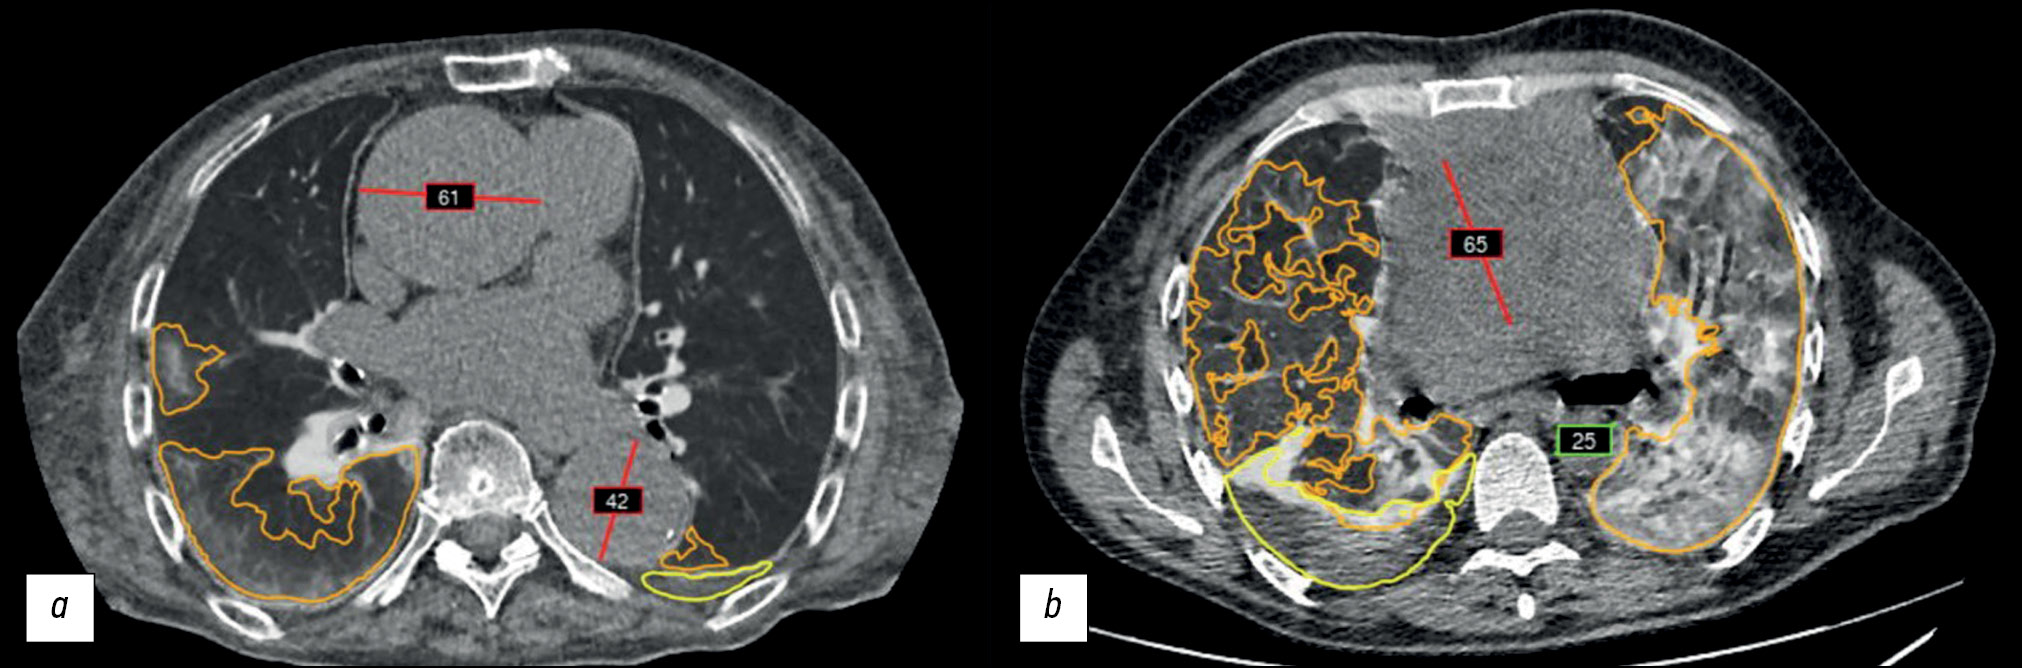

An example of an AI technology algorithm operation is presented in Fig. 2.

Fig. 2. An example of an algorithm operation of a complex AI-based service to process chest CT findings: a: AI technology correctly selected and marked (red line) the suspected ascending and descending thoracic aortic aneurysms; b: a false positive result: a mediastinal neoplasm was marked (red line) together with the ascending thoracic aorta; the green frame indicates the diameter of the descending thoracic aorta. This complex AI-based service has additional modules for marking pulmonary infiltrates (orange outline) and pleural effusion (yellow outline).

The AI technology algorithm was used to process 84,405 noncontrasted chest CT scans for detecting abnormal thoracic aortic dilatation. In total, 86 patients (62 male and 24 female patients) with a suspected thoracic aortic aneurysm according to AI technology findings were selected from this sample and retrospectively reviewed by radiologists and vascular surgeons. Of 86 patients, six were excluded from the sample because no protocol was available in the ERIS, and five had a false positive result after AI data processing (assessment of a nontarget pathology or organ, Fig. 2, b); these five patients were also excluded from the sample.